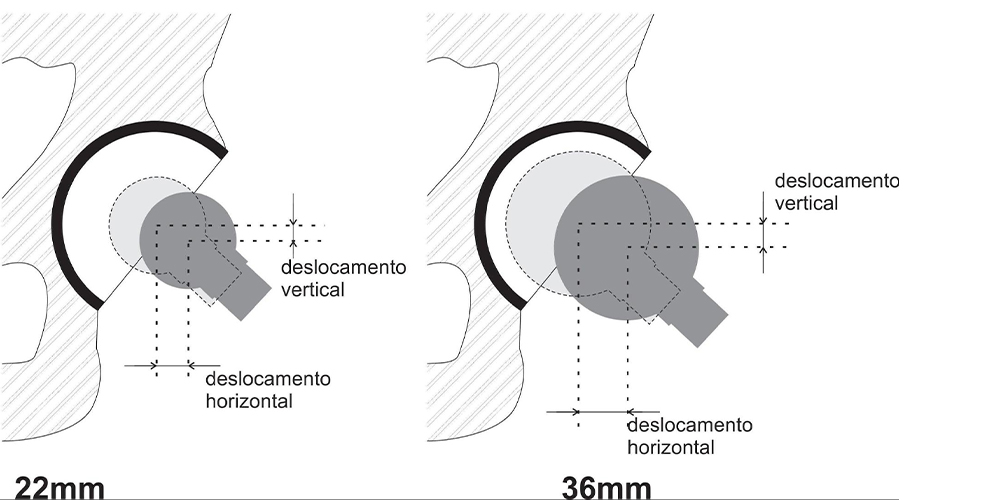

O tamanho da cabeça femoral é outro fator que interfere no resultado final do procedimento. Nos casos de artroplastias que utilizam cabeças maiores, estas possibilitam maior amplitude de movimento. O sistema de Charnley com cabeça 22mm proporciona um arco de movimento de 90º, comparado com 118º no sistema Amstutz com uma cabeça de 28mm. As cabeças maiores também apresentam maior estabilidade, já que os deslocamentos verticais e horizontais necessários para que haja luxação são maiores (Fig. 6) (7).